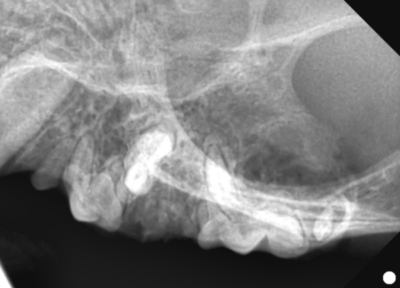

そして歯科レントゲン撮影を行いました。

なにがなにやらわからないと思い、黄色ラインで歯をなぞりました。右上顎です。中央に過剰な歯があり、回転して生えています。

右上顎も同様に中央に回転して生えている過剰歯があります。